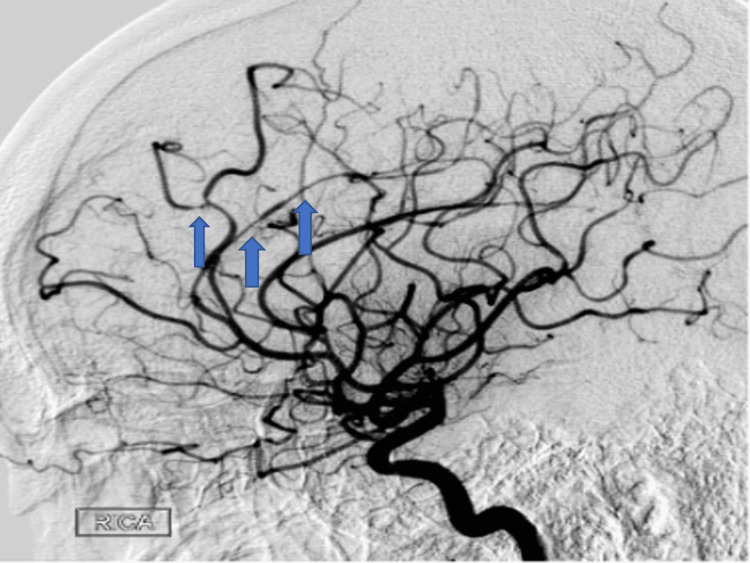

Less than 30 days later, the patient returned to the hospital with new mild expressive aphasia and right-sided facial droop. The patient endorsed that he was still experiencing headaches, which he continued to describe as thunderclap in nature. MRI of the brain without contrast revealed multiple acute punctate infarcts in the left frontoparietal area (Figure 1c). CTA Head and Neck with contrast demonstrated findings concerning for new stenosis of the distal right M1 (Figure 1d), which was not seen on the initial CTA. UDS resulted positive for THC again. Digital subtraction angiography (DSA) was done and revealed multifocal narrowing and beaded appearance of the intracranial circulation, greater on the right than the left. RCVS was the leading differential at this time given the patient’s reported thunderclap headaches, cerebral vessel imaging findings of multifocal narrowing and progression of intracranial vessels compared to prior vessel imaging, and persistent use of THC. Given the beaded appearance noted on DSA, the patient underwent a lumbar puncture to assess for the possibility of central nervous system vasculitis. Cerebrospinal fluid studies obtained from the lumbar puncture were within normal limits. Following the clinical improvement of neurological symptoms, the patient was started on nimodipine for symptomatic treatment of headaches and prevention of further vasospasm of cerebral arteries. Upon discharge, he was extensively counseled on medication compliance for outpatient nimodipine, recommended to abstain from THC use, and advised to perform a repeat CTA Head and Neck with contrast outpatient in three months to further assess intracranial vasculature.

Three months after discharge, the patient underwent repeat DSA, which revealed persistent multifocal stenosis throughout the intracranial circulation with minimal progression in the distal right MCA.